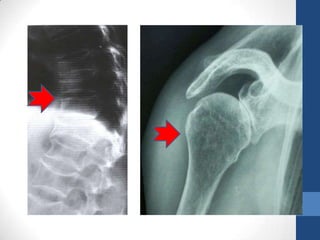

Radiografía

• Detecta Alteraciones Con Perdida Del 30-50% Del

Mineral Óseo

• Perdida De Altura Del Cuerpo Vertebral (Anterior

Y Media)

Imágenes Radiografía •Detecta Alteraciones Con Perdida Del 30-50% Del Mineral Óseo • Perdida De Altura Del Cuerpo Vertebral (Anterior Y Media) Ultrasonógrafia Del Calcáneo • Mide La Densidad Y Estructura Del Hueso “Calidad” • Predice Riesgo De Fracturas